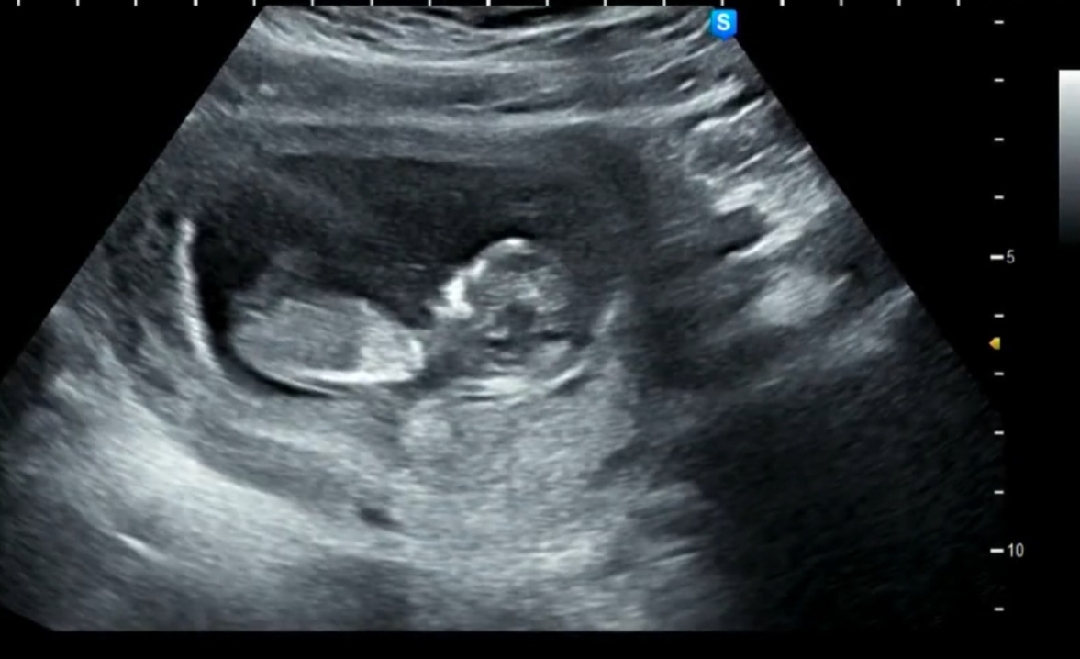

11주 4일 각도법 고수님들!!

각도법 고수님들 고견 부탁드립니다❤️🥺